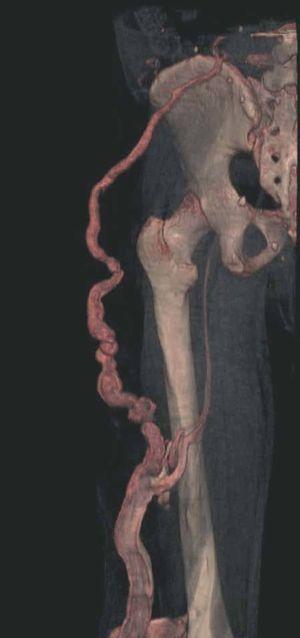

Hoy en día la utilización de los nuevos equipos TC multicorona y RM permiten la adquisición de imágenes con gran rapidez, pudiendo realizar reconstrucciones multiplanares de gran calidad, así como estudios angiográficos no invasivos13,23. Recientemente hemos estudiado 16 pacientes con síndrome de Klippel-Trenaunay mediante una venografía tomografía computarizada multicorte (TCM) o una venografía resonancia magnética tridimensional (RM-3D), utilizando imágenes axiales convencionales, reconstrucciones multiplanares (RMP), proyecciones de máxima intensidad (PMI) e imágenes tridimensionales (figs. 1-3). Las imágenes axiales convencionales fueron de utilidad para evaluar el tejido blando y el hueso y permitieron localizar el sistema venoso profundo y los vasos anómalos superficiales, determinando su relación con estructuras adyacentes. Las imágenes axiales, RMP y PMI fueron empleadas para trazar el origen, trayecto y extensión de las malformaciones venosas. Las imágenes de la superficie cutánea permitieron evaluar la localización y la extensión de la mancha en vino de Oporto y demostrar la hipertrofia de la extremidad. Las reconstrucciones tridimensionales permitieron demostrar las varicosidades y el origen y trayectoria de los vasos aberrantes (figs. 4 y 5). Ninguno de los pacientes requirió otra técnica complementaria invasiva (flebografía convencional) para confirmar el diagnóstico y planificar las estrategia terapéutica24.

Figura 5. Hipertrofia músculo-esquelética e hipoplasia de vena femoral superficial en paciente con síndrome de Klippel-Trenaunay.